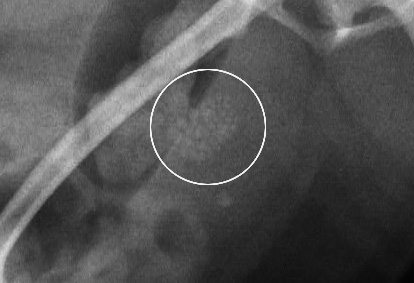

ポメラニアン オス6才 にできた膀胱結石

1mm大の結石が多数

酸性尿酸ナトリウム結石

ストルバイト結石